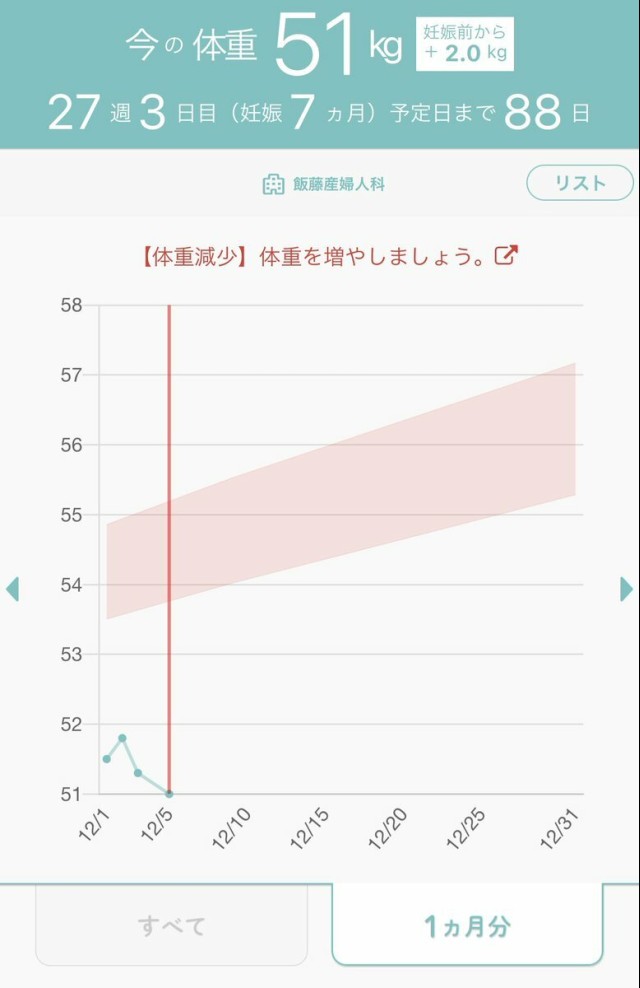

体重管理 ご飯もお菓子もしっかり食べてる方だと思うけど、妊娠前が大食いだったからか体重がなかなか増えない けど赤ちゃんは1000g超えてすくすく育ってるみたいだから病院で指摘されるまでは気にせず過ごします〜 昨日は夜ごはんのお米を炊くの忘れて、米なしにしたからガクッと落ちたのかも??